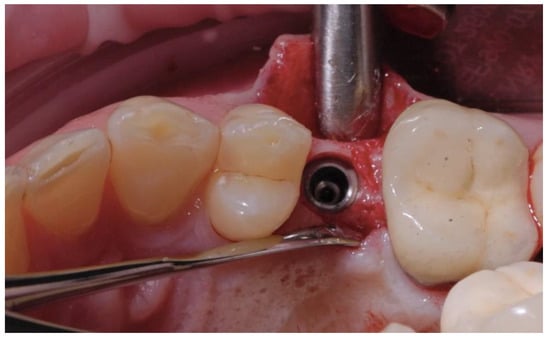

2.2. Surgical Procedures

2.3. Prosthetic Protocol